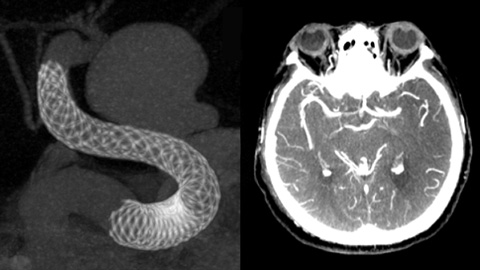

VasoCT IA ist ein Erfassungsverfahren, das ein hochauflösendes XperCT mit Kontrastmittelinjektion kombiniert, um die Visualisierung von endovaskulären Implantaten, Flow Divertern und anderen Implantaten sowie der Gefäßmorphologie bis auf Perforatorebene zu verbessern. Es wird zunehmend für die Nachuntersuchung von mit Flow Diverter Implantaten behandelten Aneurysmen verwendet, um die Positionierung des Implantats zu überprüfen.

Moderne Devices zur Behandlung zerebraler Aneurysmen sind teilweise nur sehr schwierig erkennbar, wodurch sich die Dauer solcher Eingriffe erheblich verlängern kann. Deshalb ist eine exzellente 2D- und 3D-Bildgebung wichtiger denn je, denn sie erleichtert die Entscheidungsfindung wie auch die Implantat-Platzierung und ermöglicht gleichzeitig eine effiziente Kontrolle der Strahlendosis.

Die Möglichkeit zur Darstellung der vaskulären Anatomie und endovaskulärer Materialien im Submillimeter-Bereich verbessert die Erfolgschancen und erhöht die Behandlungssicherheit. XperCT bietet CT-artige Bilder, die direkt in der Neuro Suite erfasst werden und die Identifizierung diskreter Weichgewebeläsionen erleichtern. Eine Kontrolle des Behandlungserfolgs ist somit noch im Untersuchungsraum möglich. VasoCT bietet 3D-Bildgebung mit hoher Auflösung, die wichtige zerebrovaskuläre Strukturen darstellt und so die räumliche Beurteilung von Gefäßen im Weichgewebe auf höchstem Niveau unterstützt.